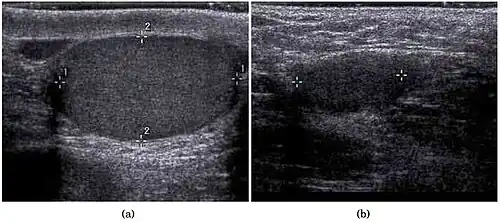

Scrotal ultrasonography of undescended testis: (a) Normal testis in the scrotum (b) Atrophic and decreased echogenicity of the contralateral testis of the same patient seen in the inguinal region

In the minority of cases with bilaterally nonpalpable testes, further testing to locate the testes, assess their function, and exclude additional problems is often useful. Scrotal ultrasound or magnetic resonance imaging performed and interpreted by a radiologist can often locate the testes while confirming the absence of a uterus. At ultrasound, the undescended testis usually appears small, less echogenic than the contralateral normal testis and usually located in the inguinal region. With color Doppler ultrasonography, the vascularity of the undescended testis is poor.